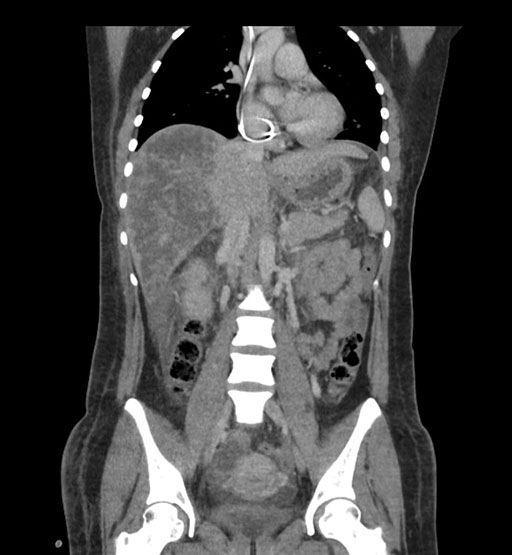

Coronal Arterial

Coronal Venous

Imaging analysis

Based on initial findings, which issue(s) would you be most concerned about?